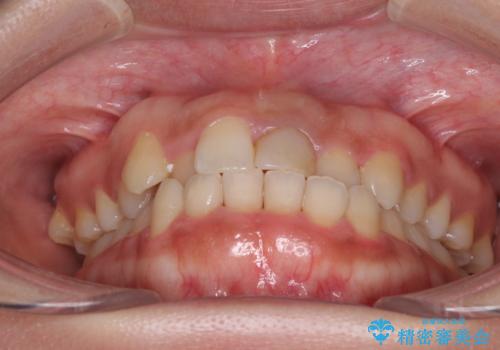

前歯の反対咬合 非抜歯のワイヤー矯正

- 前歯のでこぼこを気にして来院された患者様です。

マウスピース矯正の自己管理が面倒くさいことと、治療を早く終わらせたいとのことで、目立ちにくいワイヤー矯正にて歯列を整えることとしました。

1年半はかかると思っていた治療期間ですが、反対咬合となっている前歯が思いの外早く動き、僅か9ヶ月で終了させることができました。

前歯を気にせず笑えるようになり、患者様には大変満足していただきました。